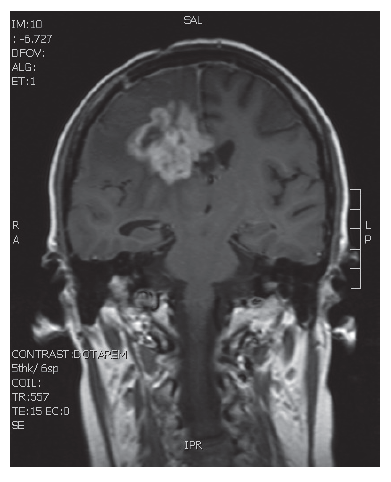

V naší kazuistice prezentujeme 25letou pacientku s negativní onkologickou rodinnou anamnézou, která dosud vážněji nestonala. Udávala asi 3 měsíce progredující bolesti hlavy a krční páteře, zvracení, postupně rozmazané vidění a parestezie horních končetin. Byla provedena magnetická rezonance, na které diagnostikován tumor mozku ve frontálním laloku vpravo, vyplňující frontální roh postranní komory velikosti 6x5 cm, midline shift, mass efekt. Dne 23. 9. 2013 ji byla na neurochirurgické klinice provedena neradikální exstirpace tumoru z parasagitální kraniotomie. Histologicky byl prokázán glioblastom multiforme gr. IV. Od 30. 10. 2013 do 12. 12. 2013 absolvovala konkomitantní radiochemoterapii (radioterapie do CLD 60,0 Gy) s temozolomidem (75 mg/m2 per os D1-42). Od ledna do dubna 2014 pokračovala v chemoterapii temozolomid solo v dávce 150 mg/m2, resp. od 2. cyklu 200 mg/m2 D1-5 ( Temodal tbl, celkem 4x). Na kontrolní MRI mozku ze dne 20. 5. 2014 byla prokázána progrese rezidua. Dne 4. 6. 2014 podstoupila druhou operaci, histologicky verifikován glioblastom multiforme s přechodem v gliosarkom. Snažili jsme se získat informace ze zahraniční literatury s léčbou gliosarkomu, bohužel se jedná o velmi vzácné onemocnění a údajů není mnoho. Nakonec byla zvolena léčba podle protokolu ICE (ifosfamid, carboplatina, etoposid), který je obdobou režimu PEI. Dávky: ifosfamid 1000 mg/m2 D1-3, carboplatina 110 mg/m2 D1 a etoposid 100 mg/m2 D1-3 v pětitýdenním cyklu. Pacientka zahájila 1. sérii od 1.7.2014 s podporou G-CSF (Neulasta s.c.). Léčbu tolerovala dobře, bez akutních či pozdních vedlejších nežádoucích účinků a významné hematologické toxicity. Po 3 cyklech podstoupila kontrolní MRI, kde popsána parciální regrese periferního sycení – rezidua tumoru. Po dalších 3 cyklech chemoterapie provedena restagingová MRI, kde popsána opět mírná regrese rezidua tumoru. Celkový stav pacientky se během léčby postupně zlepšoval, je mobilní, bez psychoorganického syndromu. Byly vysazeny kortikoidy, což vedlo k ústupu cushingoidního syndromu. Bylo rozhodnuto o pokračování v dalších 2 cyklech udržovací chemoterapie, na kontrolní MRI ze 14. 4. 2015 a 7. 7. 2015 popsána stabilizace onemocnění.